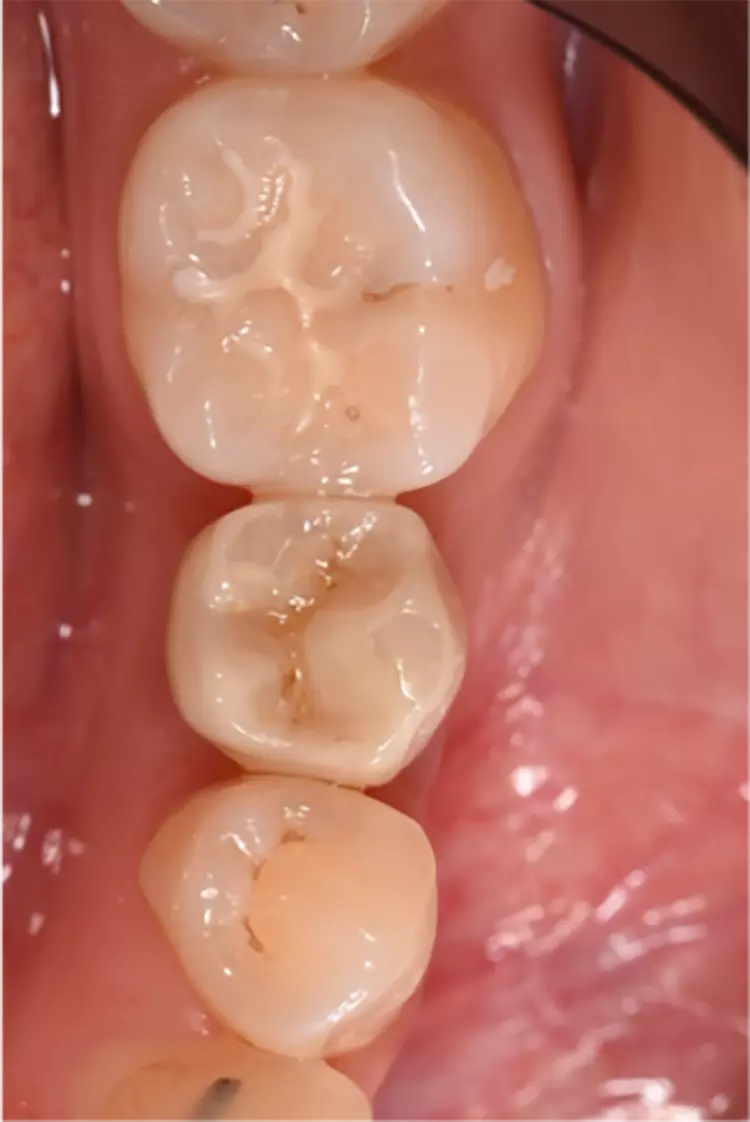

Die Implantate wurden im üblichen chirurgischen Vorgehen inseriert und sofort mit einem Provisorium aus Polymethylmethacrylat (CAD-Temp, VITA) versorgt, wobei die Provisorien außer Okklusion geschliffen wurden und darauf geachtet wurde, dass approximal nur sehr schwache Kontakte bestanden (Abb. 3a bis e). Die definitive prothetische Versorgung erfolgte im Unterkiefer nach frühestens 2 Monaten, im Oberkiefer nach frühestens 4 Monaten. Die Restaurationen wurden aus verblendetem Zirkonoxid hergestellt (VITA YZ HT / VITA VM 9, VITA).

Nach einem Jahr konnten 67 Implantate [27], nach 3 Jahren 65 Implantate [5] und nach 5 Jahren 63 Implantate [4] nachkontrolliert werden. Es gab einen Frühverlust nach 5 Wochen.

Die Überlebensrate betrug wie oben bereits erwähnt nach 5 Jahren 98,4%. Die 7,5-Jahres-Daten mit unverändert stabilen klinischen Ergebnissen sind erhoben worden und die Veröffentlichung ist in Vorbereitung.

Dies wird als Remodelling infolge des chirurgischen Eingriffs gewertet. Im weiteren Verlauf war kein zusätzlicher Knochenverlust zu beobachten. Die Ergebnisse sind besonders unter dem Aspekt zu betrachten, dass die Implantate sofort nach der Implantation mit Provisorien versorgt wurden und somit bereits unmittelbar nach dem Setzen ? wenn auch eingeschränkt ? funktionell belastet wurden. Insgesamt sind dies trotz der beiden Verluste ausgezeichnete Ergebnisse und man darf sagen, dass dieser Implantattyp hervorragend osseointegriert.